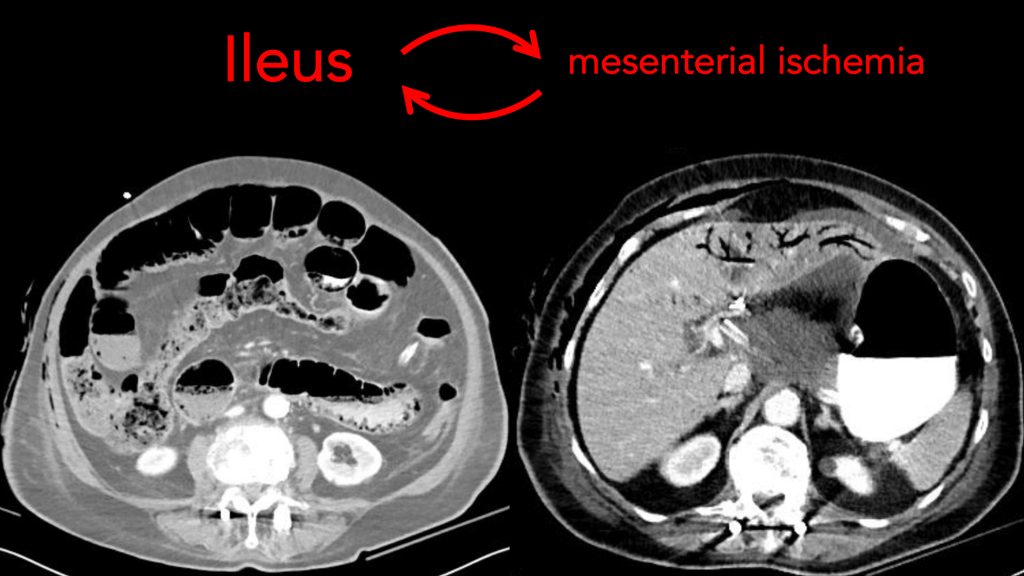

NOMI